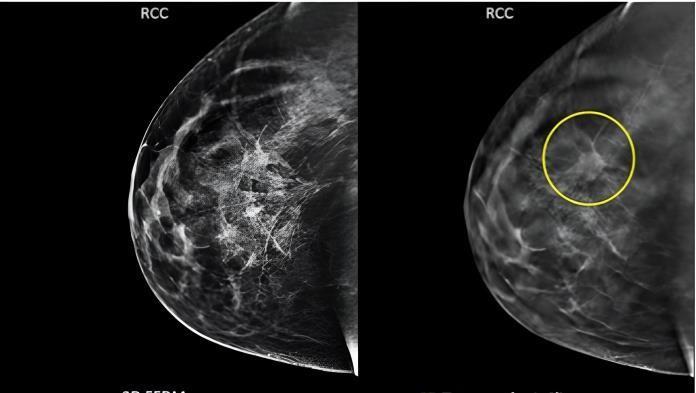

Figure4illustrateshowthelocation,size,andstageofbreast cancermightaffectitsappearanceonmammograms.Tofind breast cancer, radiologists look for anomalies and trends. Masses, microcalcifications, and architectural deformities are typical findings.Nodules, spiculated borders, and asymmetries. Microcalcifications are microscopic calcium deposits in breast tissue, whereas masses, microcalcifications,andarchitecturalabnormalitiesareearly indicatorsofbreastcancer.K-foldcross-validationisabreast cancerscreeningmethodthatdividesadatasetintoKequalsizedsubgroups.TheotherK-1subsetsareusedfortraining, andoneoftheKsubsetsisusedasthetestset.Kevaluations and trainings are performed on the model. Performance metricsarecalculatedonthetestsettoassesshowwellthe model generalizes to new data. After all K iterations, the performancemetricsfromeachfoldareaveragedtoprovide acomprehensiveoverview.